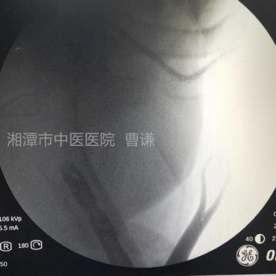

外伤后拍片示:右股骨中下段粉碎性骨折